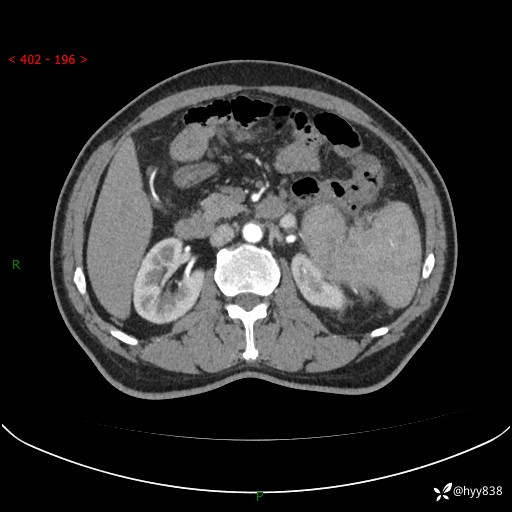

上腹部CT平扫

增强(动脉期+静脉期)